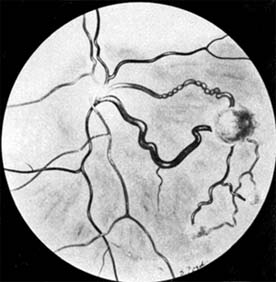

Presumed Ocular Histoplasmosis Syndrome (Figures 10-5, 10-6 and 10-7)

In this disease, serous and hemorrhagic detachments of the macula are associated with multiple peripheral atrophic chorioretinal scars and peripapillary chorioretinal scarring (see Chapter 7). The syndrome usually occurs in healthy patients between the third and sixth decades of life, and the scars are probably caused by an antecedent subclinical systemic infection with Histoplasma capsulatum. The macular detachments are due to subretinal neovascularization, and the visual prognosis depends on the proximity of the neovascular membrane to the center of the fovea. If the membrane extends inside the foveal avascular zone, only 15% of eyes will retain 20/40 vision. A macular scar may change over time, and 10% of patients with normal maculae will develop new atrophic scars in this region. The relative risk of developing macular subretinal neovascularization in the second eye of an affected patient is significant, and these patients should be instructed in the frequent use of the Amsler grid and the importance of prompt examination when changes are detected.

Figure 10-5

Figure 10-5: Presumed ocular histoplasmosis syndrome with active disease (large arrows) and an inactive pigmented macular scar (small arrow). Peripapillary pigmentation (curved arrow) is also present.

Figure 10-6

Figure 10-6: The early fluorescein angiogram shows an inactive hypofluorescent scar (small arrow) and the characteristic lacy hyperfluorescence of subretinal neovascularization (open arrows).

Figure 10-7

Figure 10-7: Late fluorescein leakage from macular subretinal neovascularization in a patient with presumed ocular histoplasmosis syndrome.

Argon laser photocoagulation of a subretinal neovascular membrane outside the foveal avascular zone in symptomatic patients is of value in preventing severe vision loss. The surgical removal of submacular membranes may prove useful in preserving vision.